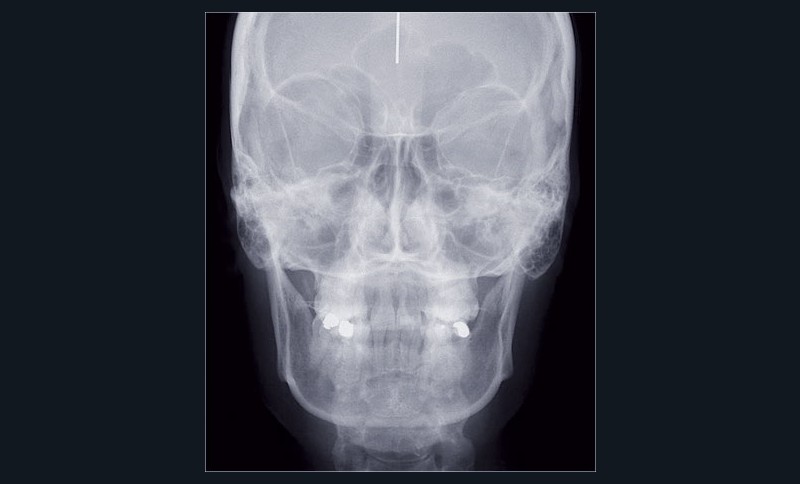

Cas n° 2

Nous lui avons donc proposé un traitement d’alignement avec maintien des 14 et 24 en position de 13 et 23 et optimisation du torque pour favoriser un développement des arcades et chercher à améliorer le sourire et le soutien labial.

La patiente donne son accord pour un appareillage Damon Insignia métal qui permet une individualisation complète des brackets dans les 3 sens de l’espace.